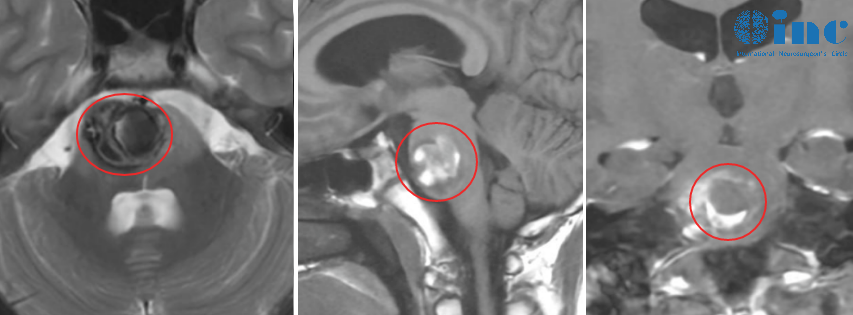

术前影像

术后半年复查:小宇复查时正值巴教授中国行期间,便想当面感谢巴教授,并还想让巴教授看看本次复查结果——恢复良好,为何MRI提示脑干异常信号,考虑海绵状血管瘤以及右侧天幕下蛛网膜囊肿呢?

巴教授给出回答:“不存在残留,在桥脑当然也没有海绵状血管瘤复发。这是含铁血黄素的残留,这对于那么巨大出血性的内生性脑干病变是正常的,并不是活跃性海绵状血管瘤。关于蛛网膜囊肿,只要没症状,就无需任何治疗,并不需要担心。”